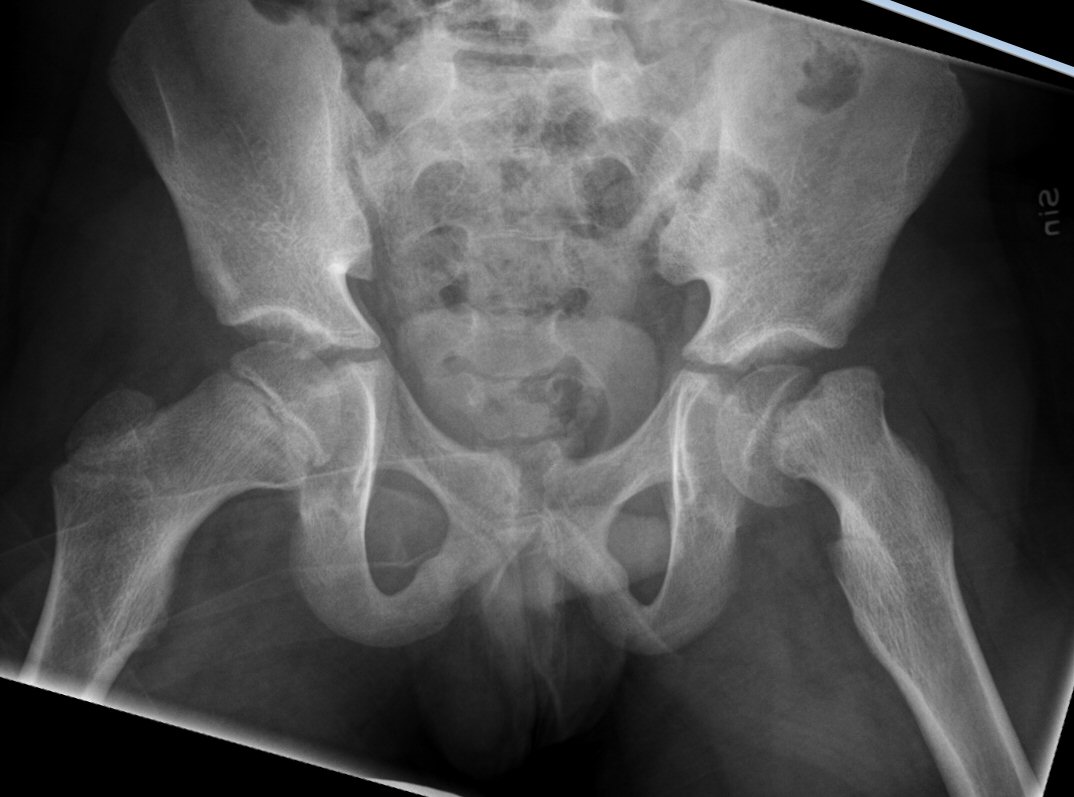

- Slätröntgen [1] av bäcken i "Lauensteinprojektion" (grodläge) och båda höfterna.

- Kleins linje - en linje längs med kollums laterala sida på frontalvy - ska gå genom kaput.

Fysiolys vänster höft akut, efter primär operation resp. innan spikextraktion efter 6 år